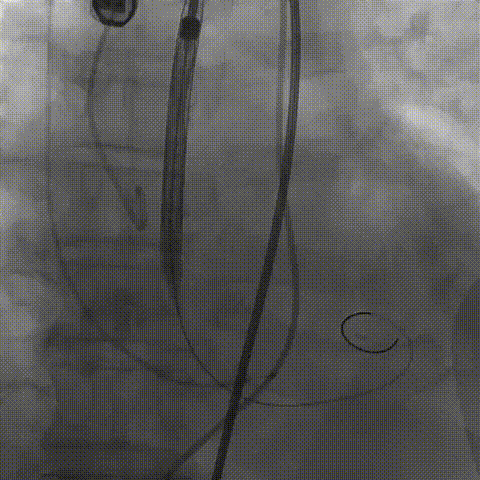

瓣膜(AV29)工作位正交体位造影位置良好,左冠显影正常

瓣膜(AV29)完全脱钩释放后23mm球囊充分后扩,冠脉灌注良好

最后造影

术后血流动力学

瓣膜工作状态良好,极微量瓣周漏,血流动力学有效改善